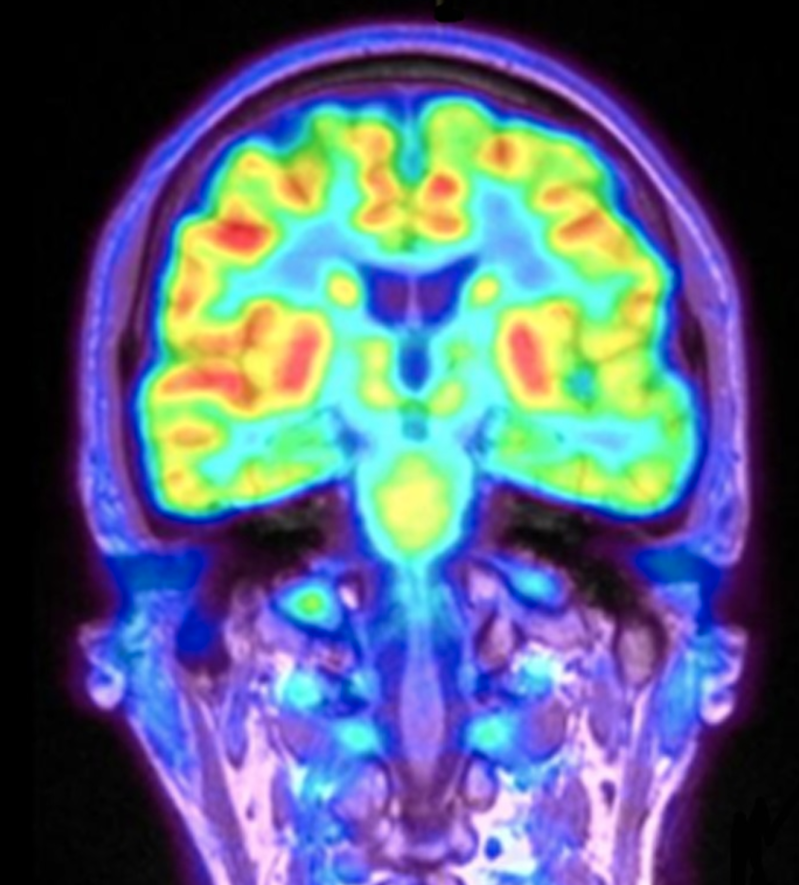

Neurologie is de medische tak die zich bezighoudt met ziekten en aandoeningen van het zenuwstelsel. Dit omvat problemen met de hersenen, het ruggenmerg, het hersenvocht, de perifere zenuwen en spieren.